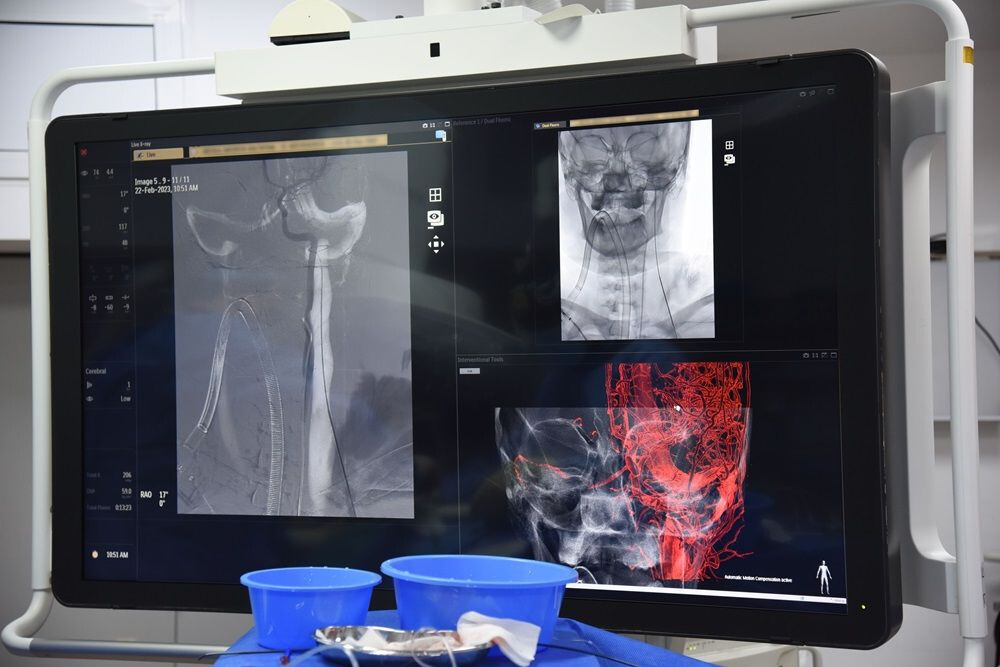

Procedură de neurodiologie intervențională pentru tratamentul unui anevrim cerebral, la Spitalul Clinic SANADOR.

În Laboratorul de Cateterism de la Spitalul Clinic SANADOR, intervențiile de neuroradiologie sunt realizate în cele mai bune condiții de confort și siguranță, cu echipamente de ultimă generație – angiografe Philips Azurion 7. Acestea asigură imagini de rezoluție superioară, clare și detaliate, cu o doză redusă de iradiere.

Laboratorul de Cateterism de la Spitalul Clinic SANADOR dispune de angiografe de ultimă generație.